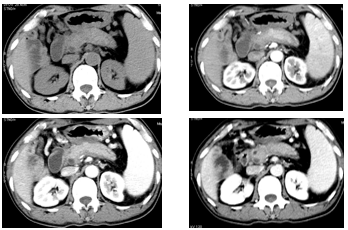

CT 表现

胰腺正常的 「 羽毛状 」 结构消失,呈现 「 腊肠样 」 外观,呈弥漫或局限性增大,可能为胰腺组织被淋巴细胞、浆细胞弥漫浸润及纤维组织高度增生而产生形态学上的变化;

胰腺周围出现增厚的包膜样结构,呈 「 鞘膜 」 征或 「 荚膜 」 征。CT 平扫呈等或稍低密度,动脉期强化较弱,呈明显的延迟强化。与胰腺纤维组织的高度增生有关。

CT 表现为胰管及胆总管下段长段狭窄,胆总管下段呈向心性狭窄,狭窄区细长,边缘光整。

弥漫性

男,58 岁,腹痛黄疸、胆肠引流术后四年,反复黑便十天

局限性

弥漫性伴胆总管改变